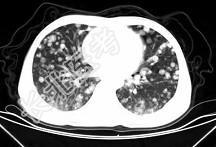

- 单项选择题男,42岁, 肝区痛一月余,最近二周咯血丝痰, 胸部CT如图,最可能的诊断为 ( )

D、肺转移瘤